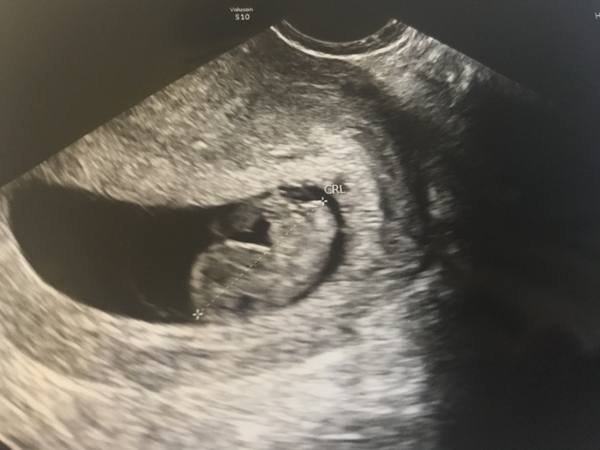

Here is my photo from the rescan this morning. 7+3/4 with a strong heartbeat. My little boy said it's a dinosaur...then a dolphin. I feel he may be disappointed with the truth.

Broke bed rest to go meet this little bean today. Had to be internal due to my uterus tilting backwards but there it was fluttering away, oblivious to the chaos it’s causing!

That's a lovely scan pic @curlypasta

@curlypasta lovely pic!

Introducing blobert. Early scan today. Baby looking well and heart beating nice and fast which is really what I wanted to know. Put me at 8+4 which is kind of what I was expecting and edd of 26th June.

Lovely scan @socktastic!

@socktastic aww blobert! 🥰

Lovely scan!